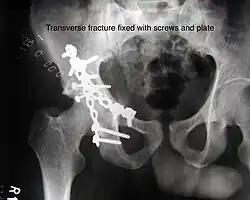

Transverse fracture showing upper iliac fragment, lower ischial and pubic fragment -

Transverse fracture fixed with screws and plate